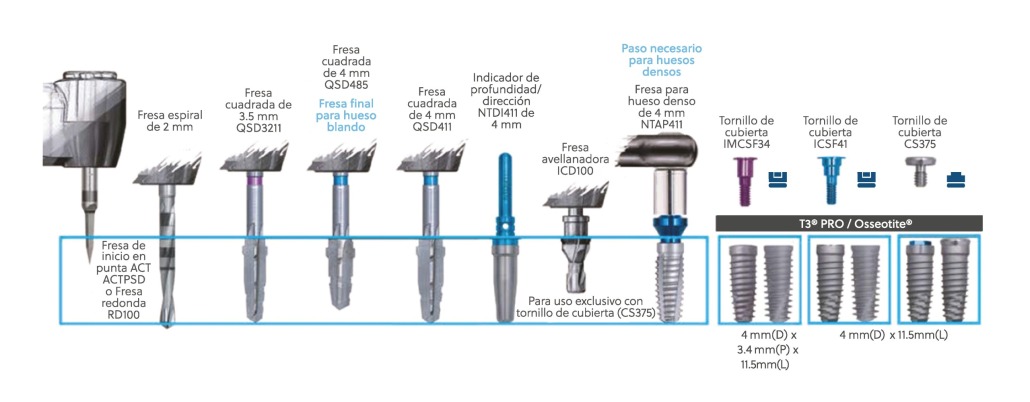

Protocolo